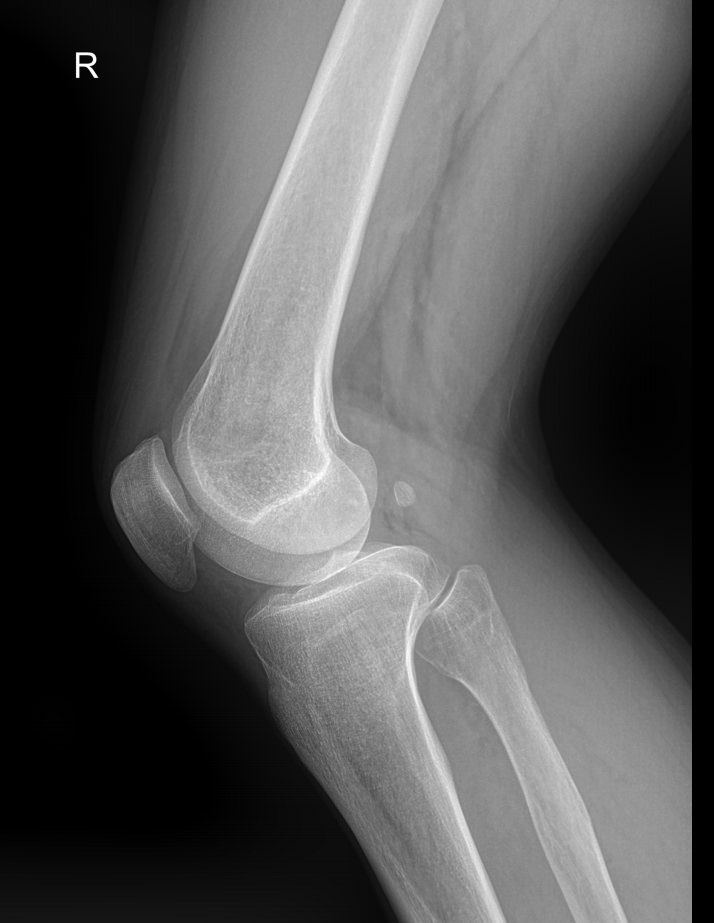

Назад Рентген обоих коленных суставов

Коленные суставы ежедневно выполняют большое количество движений, связанных с ходьбой, бегом, прыжками, приседаниями и подъемом, и выдерживают вес человека, каким бы он ни был. Как и любые другие суставы в теле, они подвержены воспалению и другим патологическим изменениям, а также травмам, инфекциям, новообразованиям и возрастным дегенеративным процессам. Это одни из самых крупных суставов в теле человека.

Первым видом диагностики пациентов с ортопедическими патологиями обычно является рентген. Это простое, быстрое, неинвазивное и безболезненное обследование с высоким уровнем информативности. В большинстве случаев его бывает достаточно для постановки диагноза и выбора тактики лечения. Кроме того, уровень облучения, который получают обследуемые, минимален благодаря современной цифровой аппаратуре.

Что покажет рентген обоих коленных суставов в одной проекции

В протоколе у каждого сустава описывается:

• Состояние мягких тканей;

• Суставная щель ― в норме, расширена, сужена, затемнена, имеет дополнительные включения;

• Состояние суставных  поверхностей и их соответствие друг другу ― несоответствие говорит о вывихе;

• Положение надколенника ― обычное или нет;

• Состояние костной ткани и надкостницы ― могут быть обнаружены участки разрежения, размягчения или других патологических процессов, а также свежие и сросшиеся переломы.